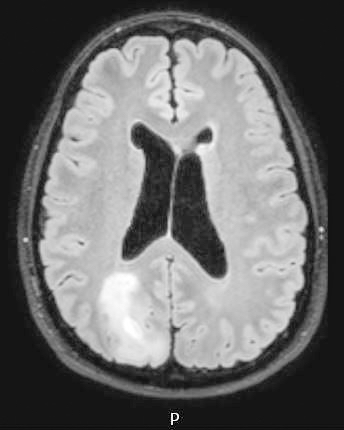

Radiology description

- CT:

- Expanding, intra-axial, poorly defined mass of low density

- Variable calcification may be seen

- Contrast enhancement and central hypodensity due to necrosis, occur with higher grades

- MRI:

- T1 hypodensity and T2 hyperintensity

- T2 hyperintensity with relative FLAIR sequence hypointensity (T2 FLAIR mismatch) is a relatively suggestive indication of IDH mutant astrocytoma (Clin Cancer Res 2017;23:6078)

- Distortion and enlargement of involved areas, including associated cortical ribbon

- Contrast enhancement is typically present in higher grade tumors (J Neurooncol 2019;141:327)

- Ring-like enhancement around central necrosis typical of grade 4

Radiology images